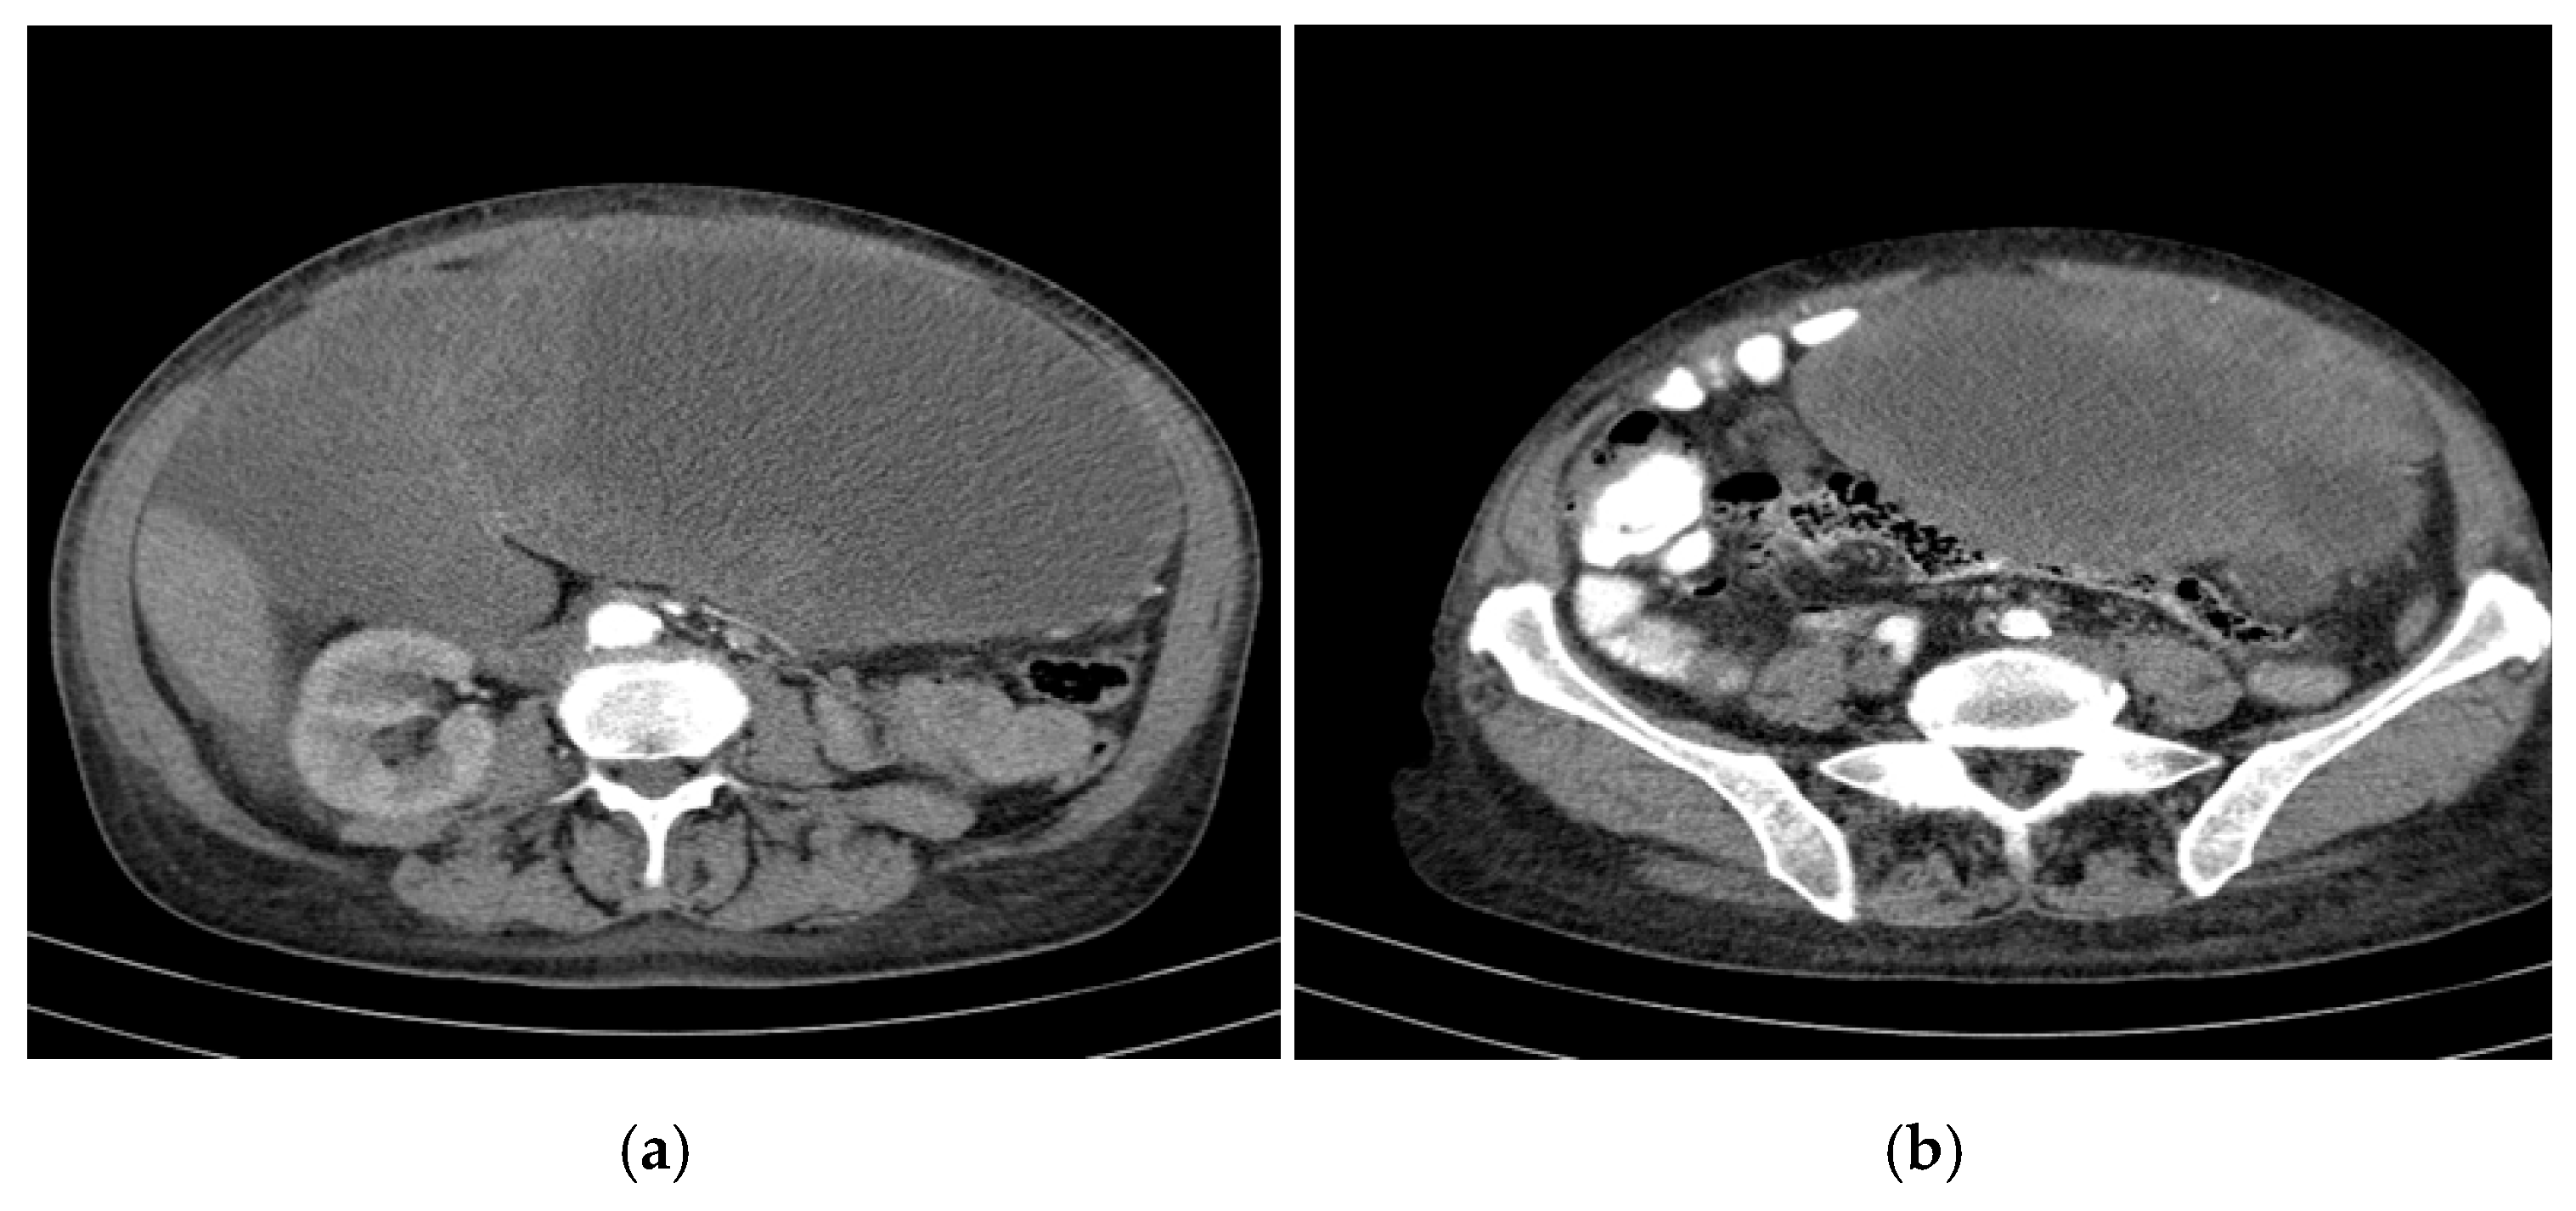

- Largest transonic formation: Located in the left abdomen with a heterogeneous circumferential wall (up to 8.3 in thickness); contained heterogeneous fluid with multiple echogenic/hyperechoic echoes, which were mobile upon compression (Figure 2).

Figure 2. CT appearance at the time of diagnosis: the inferior pole of the cystic formation in the left hepatic lobe extended into the pelvis (14/18/18.5 cm), displacing the transverse colon and small intestine posteriorly toward the right iliac fossa. (a) upper abdomen section on the left (b) pelvic section on the right.